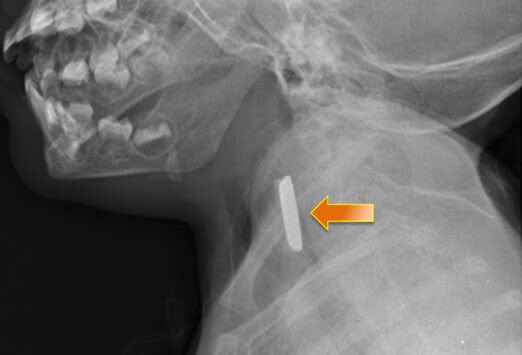

أما الخطوة الأهم فهي إجراءُ صور شعاعية